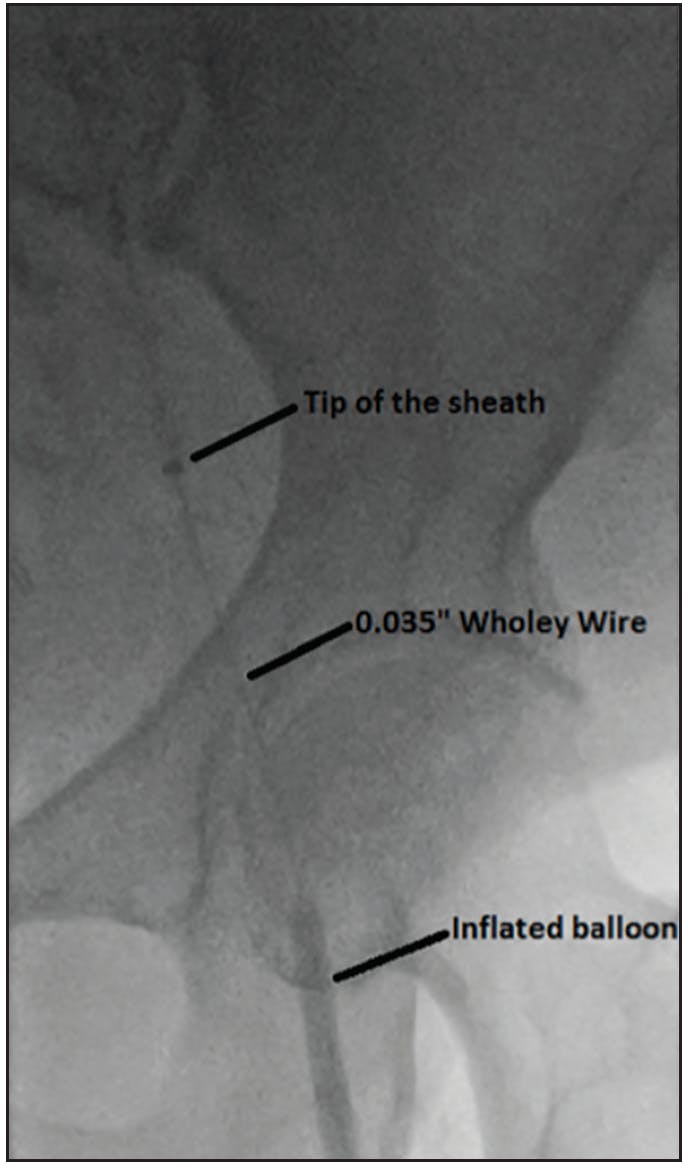

Difficulty in tracking the sheath over the wire is commonly encountered. The first step is usually to use a stiffer wire and advance it as far as it can reach. If it’s still a struggle, then apply constant pressure to advance the sheath while pulling the wire (the “paradoxical move” technique). If this does not work, then perform the “Dottering” technique by moving the wire gently backward and forward while applying constant forward pressure on the sheath to help decrease wire wall bias and center the sheath for easier advancement. If still unsuccessful, free the dilator from the sheath and walk the sheath over the dilator in small steps with a great amount of care to avoid vessel wall injury. Then, follow the sheath with the dilator and repeat walking the sheath over the dilator as needed. In extreme cases, the “balloon-assisted tracking” technique can be used. Inflate a balloon in the SFA or the profunda artery at a nominal pressure to stabilize the wire and create a strong rail over which the sheath can be advanced (Figure 1). An acute angulation of the abdominal aortic bifurcation can make wire and/or sheath advancement unfeasible despite all the previously mentioned maneuvers. In such a situation, special catheters such as a Simmons or SOS Omni can overcome this problem; however, these catheters need to be shaped in the aortic arch, and therefore heparinization is advised. The presence of kissing iliac stents makes crossover impossible, so radial access needs to be considered (Figure 2).2

Figure 1. Balloon-assisted tracking technique. In this patient, there was great difficulty advancing the sheath into the contralateral femoral system; therefore, a 5- X 40-mm peripheral balloon was inflated in the contralateral SFA at low pressure to stabilize the wire and create strong rail while pulling on the other end of the wire. This technique allowed us to advance the 6-F, 55-cm sheath easily into the contralateral CFA.